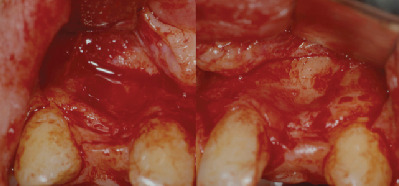

The first surgical phase was performed on an outpatient basis under local anesthesia after premedication with diazepam 0.2 mg/kg administered orally 30 minutes before surgery. Two monocortical block grafts were collected from the symphysis and fixed at the buccal aspect of the bone defects with osteosynthesis screws (Figures 3–5). At this point, DBB particles (Bio-Oss®, Geistlich Biomaterials, Wolhusen, Switzerland) and native lyophilized type I resorbable collagen membranes from equine origin (Paroguide®, GABA VEBAS srl, Rome, Italy) were used to cover the block graft at each site (Figure 6). Suture in polyamide was performed with detached stitches to obtain a first-intention seal of the flaps. Silk sutures were instead used at the donor site.

Figure 3.

Buccal view of the defects on 12 and 22.

Figure 8.

Clinical situation at 8 years.